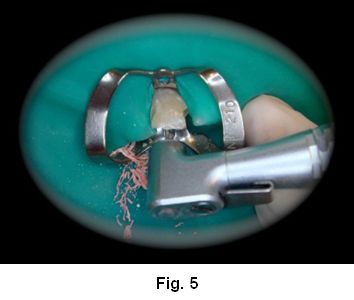

1. Tallado preliminar del conducto con fresas Largo Nº 1 y 2, respetando los 4mm de obturación remanente. (Fig. 5)